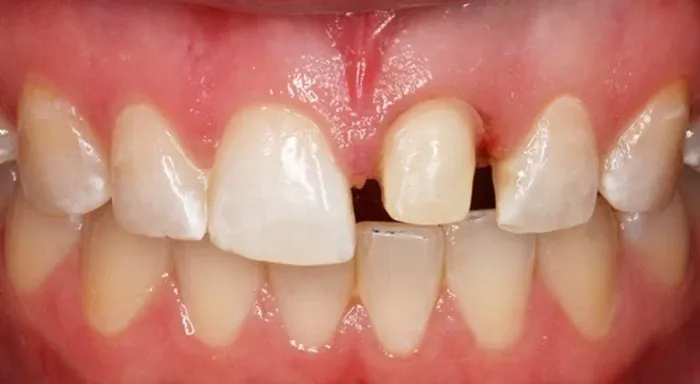

Răng Mòn và Viêm Lợi

Khi răng có dấu hiệu dài ra, nguyên nhân thường liên quan đến tình trạng tụt nướu hoặc mòn men răng. Điều này khiến phần chân răng lộ ra, làm răng trở nên nhạy cảm hơn khi ăn uống nóng lạnh. Đồng thời, tụt nướu cũng tạo điều kiện cho vi khuẩn tích tụ, dễ dẫn đến viêm lợi, chảy máu chân răng và nếu kéo dài có thể tiến triển thành bệnh nha chu ảnh hưởng đến độ chắc khỏe của răng.

Răng Dài Quá Mức

Khi nhận thấy răng lộ ra nhiều bất thường, nướu tụt rõ hoặc tỷ lệ răng – nướu mất cân đối, đó là dấu hiệu cần được kiểm tra chuyên môn. Tình trạng răng dài quá mức không chỉ ảnh hưởng đến thẩm mỹ mà còn làm tăng nguy cơ nhạy cảm răng và bệnh lý nha chu. Việc tham khảo ý kiến nha sĩ sẽ giúp xác định nguyên nhân chính xác và lựa chọn phương pháp điều trị phù hợp, tránh để tình trạng tiến triển nặng hơn.